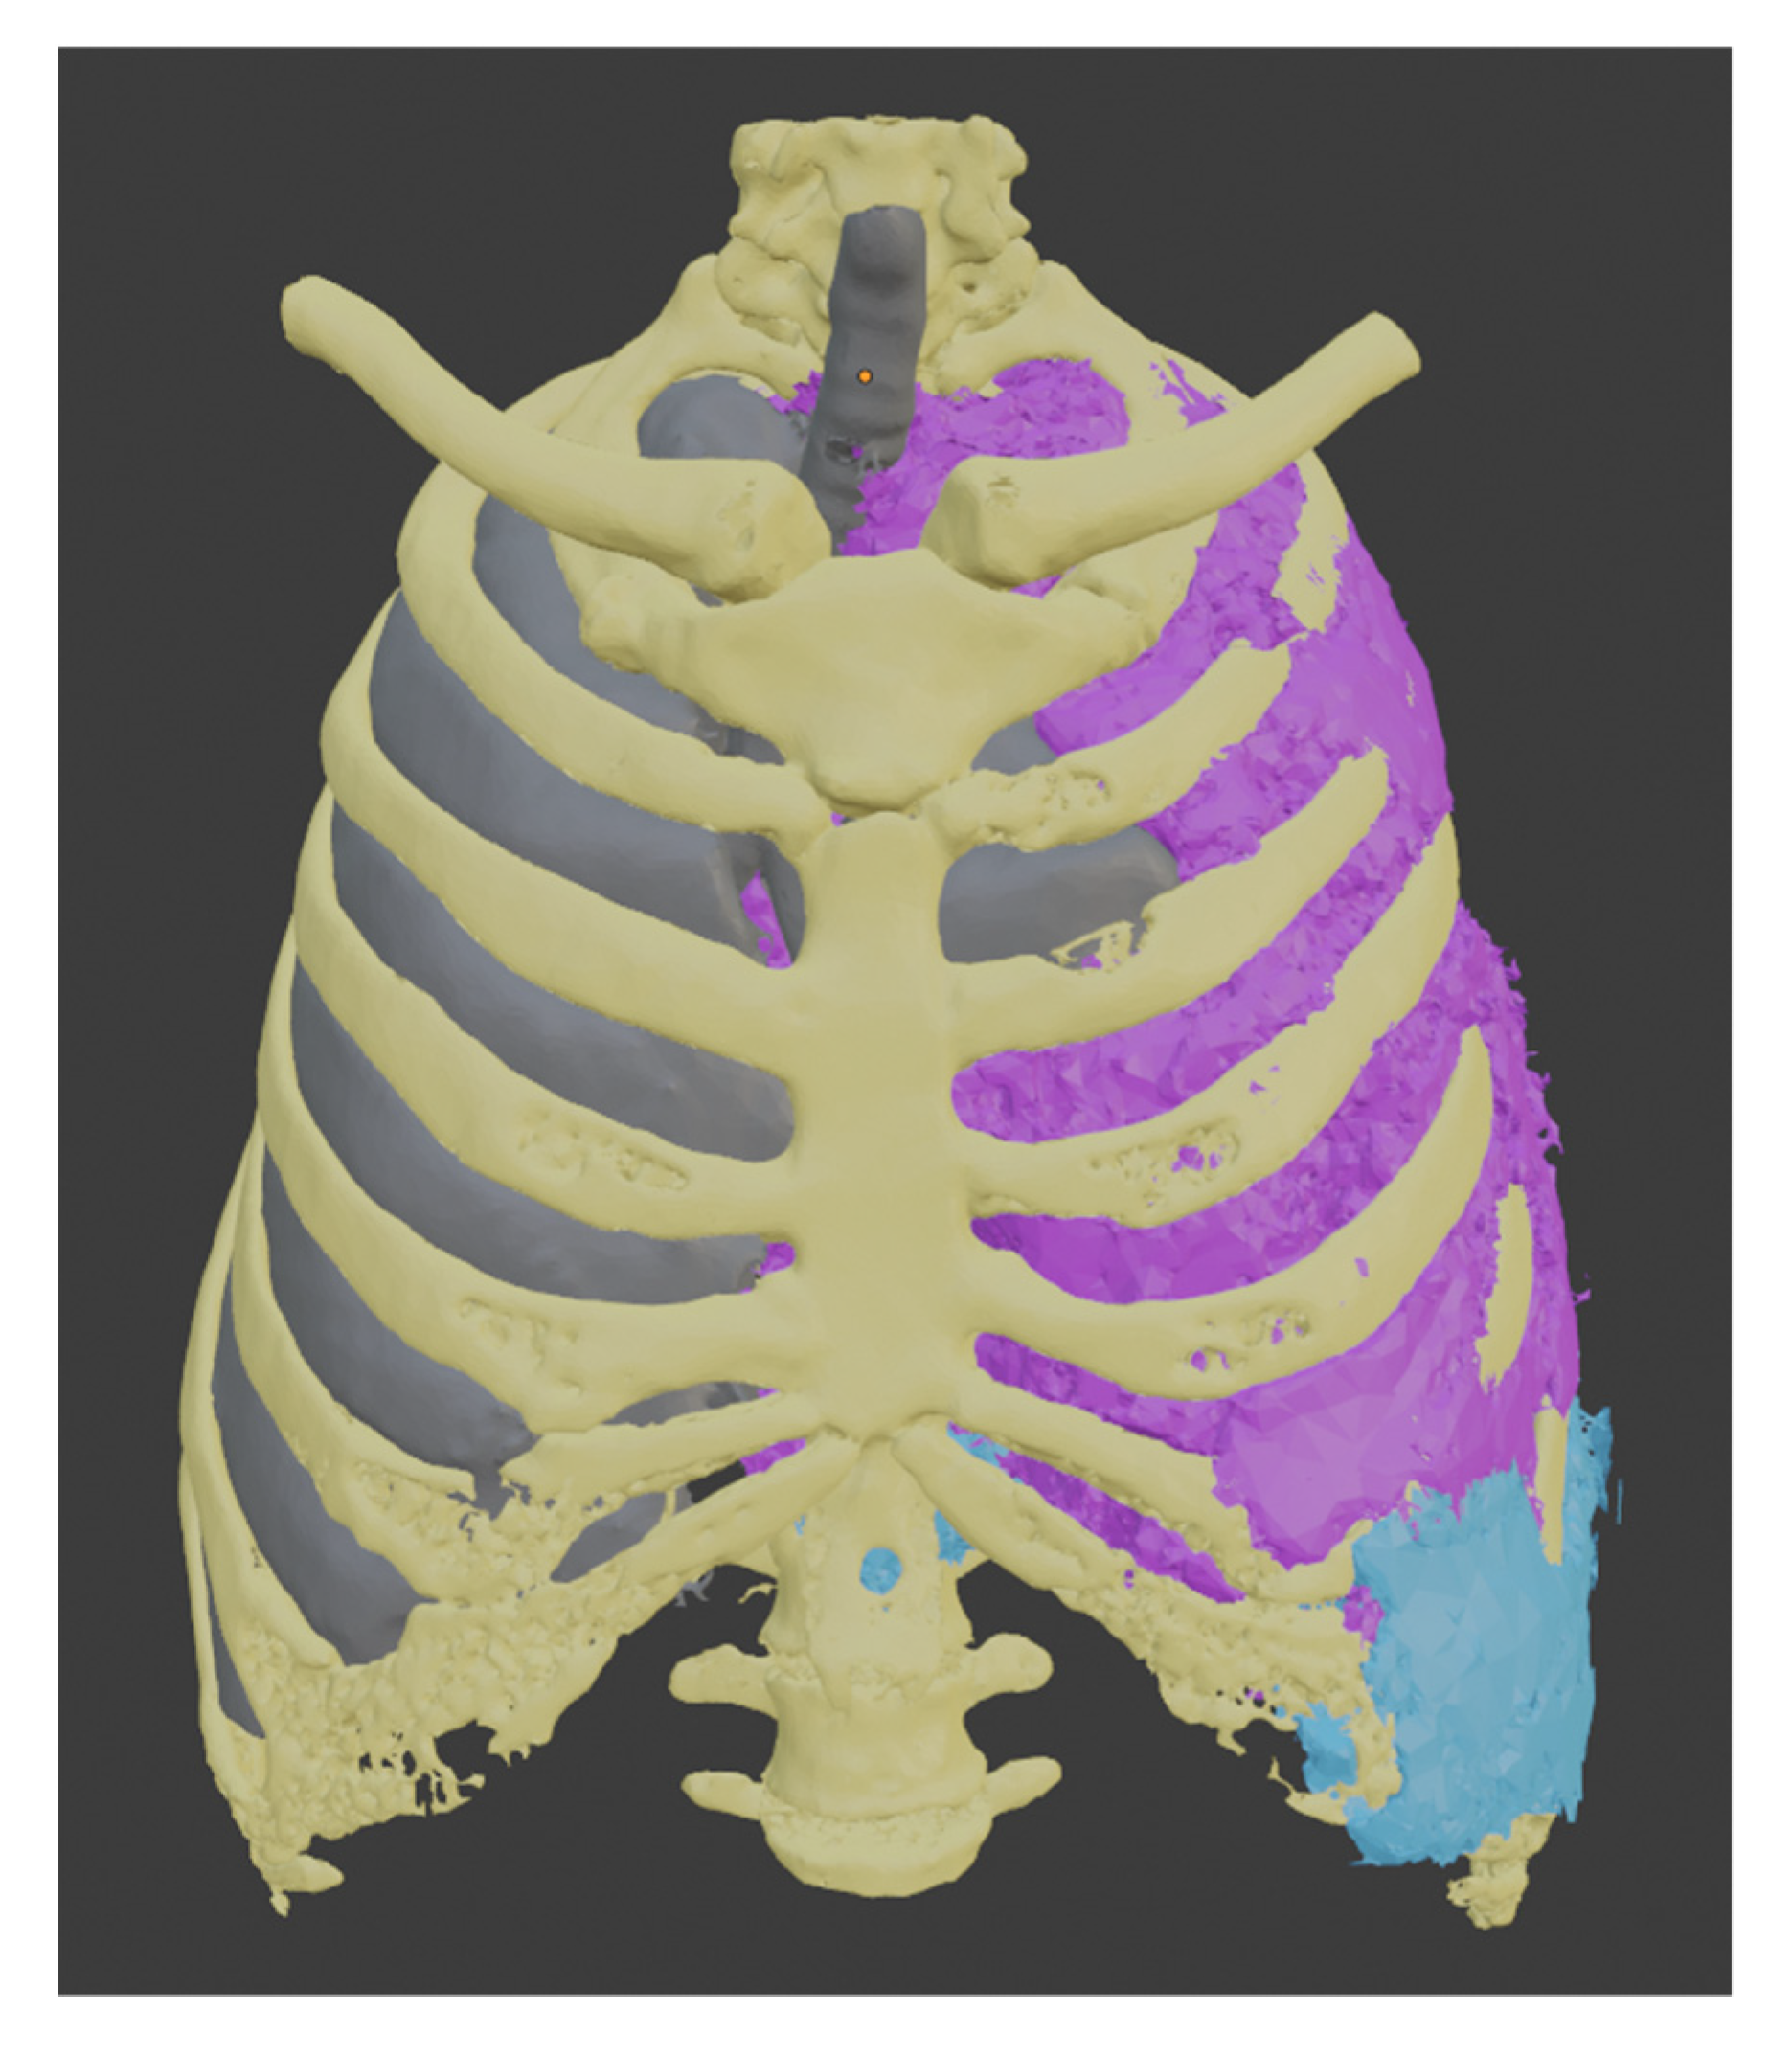

This procedure was repeated to create the liver segment, and since we have the healthy part of the lung, we used these three segments to establish the tumor’s boundaries. Each of them uses a different color, yellow for the bones, gray for the healthy part of the lung, and light blue for the liver.

To segment the tumor “Grown from seeds” tool was used, in which the internal and external edges of the tumor are delimited. This module calculates the edges of the tumor along several planes and displays them as colored areas, and these calculated borders were manually refined before proceeding to generate the tumor volume. The result was defined with purple color. We can see the union of all these segments in Figure 8.

Figure 8.

Models obtained by segmentation.

Having a visual appreciation of the segments, we know that the delimitation cannot be external to the other elements; for this reason, the “logical operator” tool was used using its “Subtract” mode of operation to remove from the tumor model all the segments that belong to other parts of the body. The resulting final model can be seen in Figure 9.

Figure 9.

Final 3d model of the tumor (A) Front view (B) Side view (C) Back view.